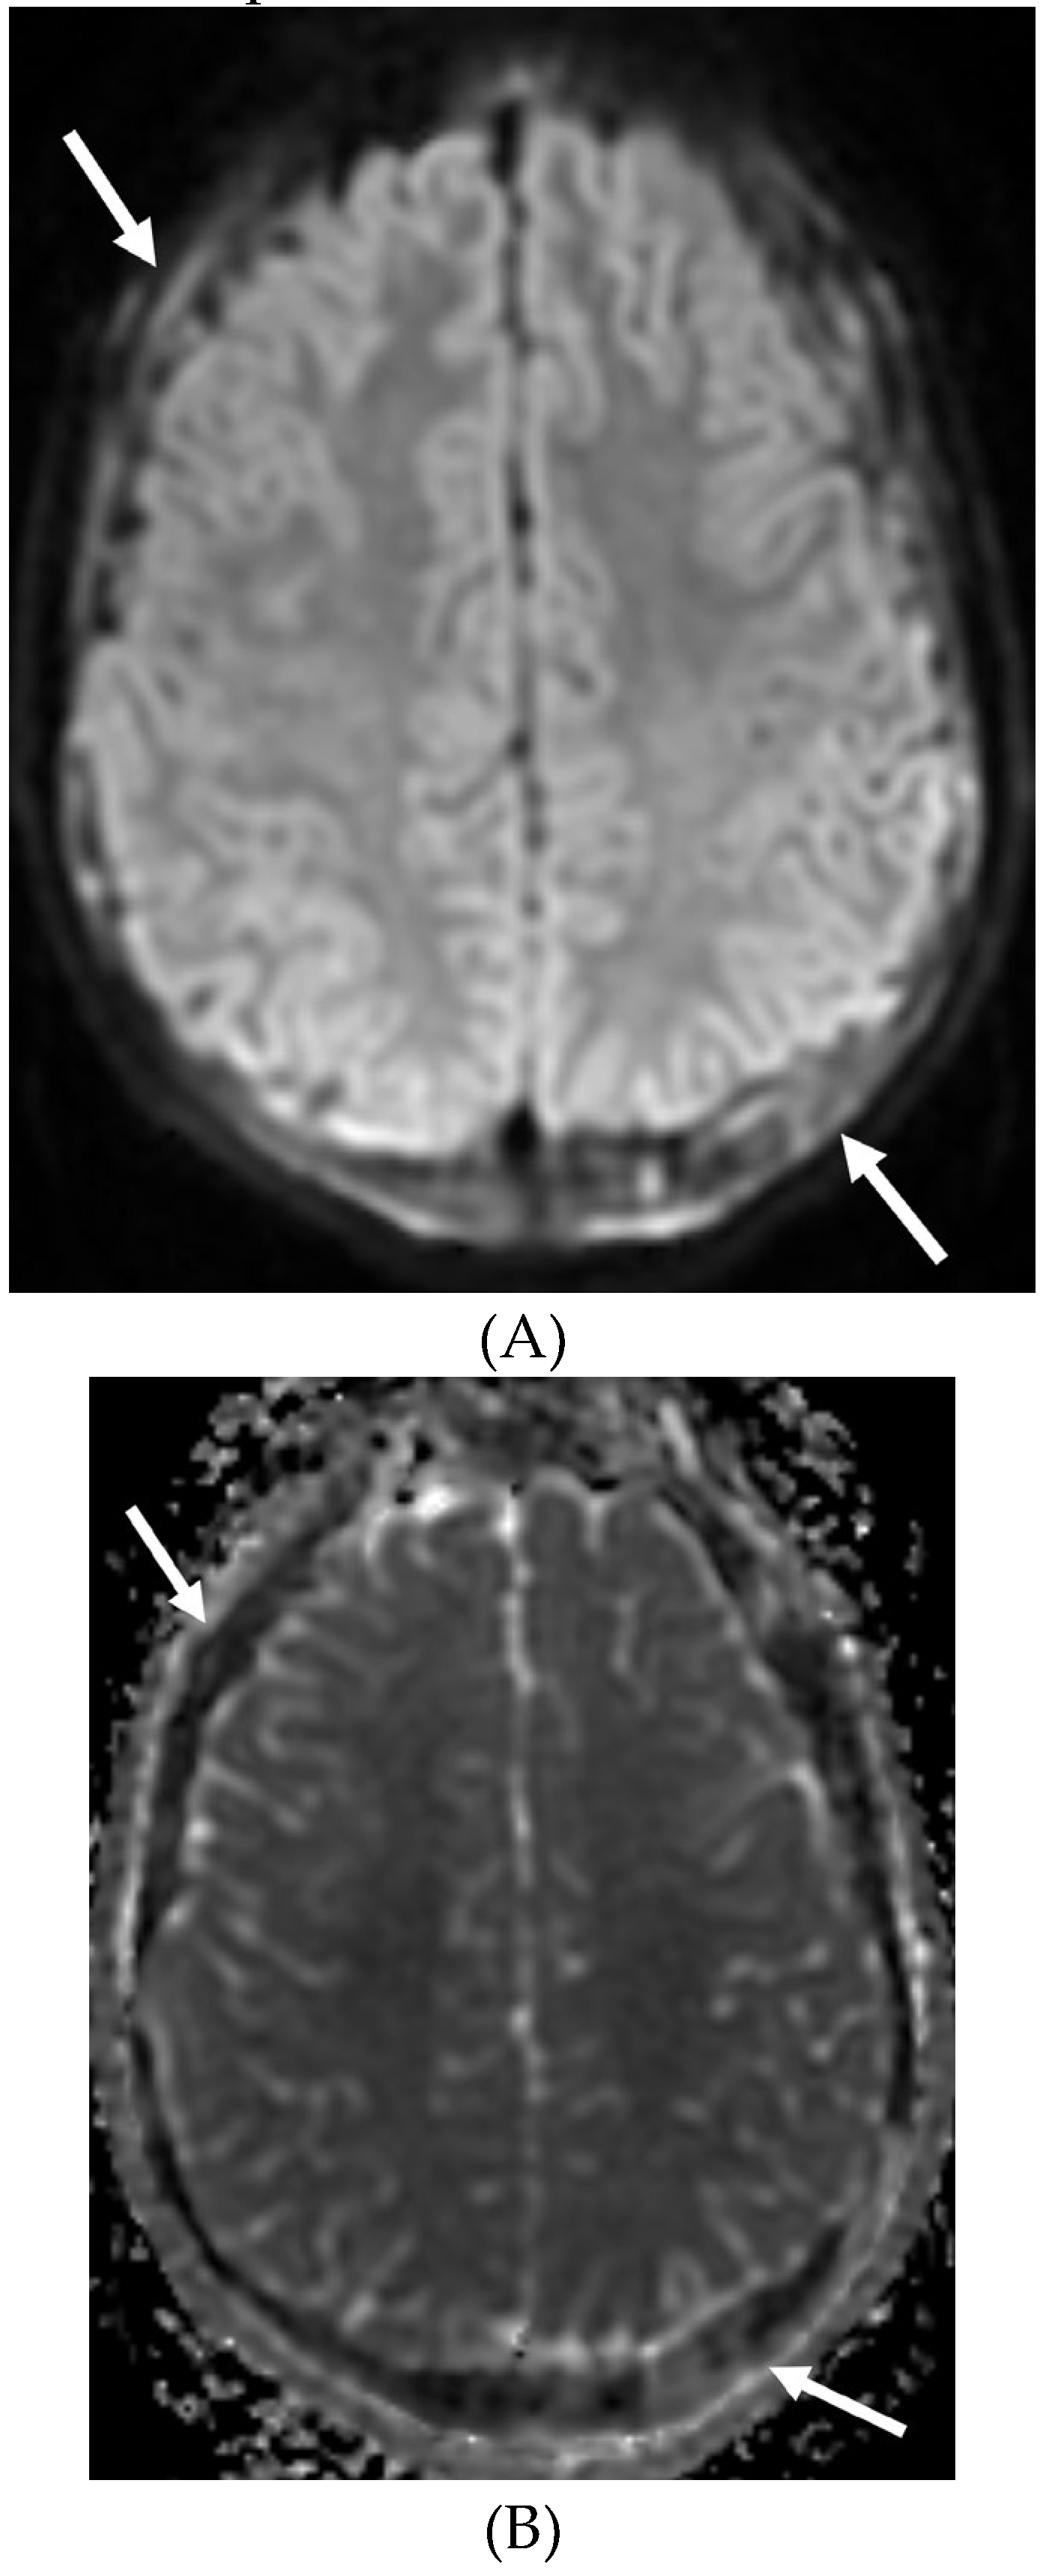

MOYA MOYA

- Horie N, Morikawa M, Nozaki A, Hayashi K, Suyama K, Nagata I. "Brush Sign" on susceptibility-weighted MR imaging indicates the severity of moyamoya disease. AJNR Am J Neuroradiol. 2011 Oct;32(9):1697-702. Epub 2011 Jul 28. PMID: 21799039; PMCID: PMC7965393. [CrossRef]

- Ohta T, Tanaka H, Kuroiwa T. Diffuse leptomeningeal enhancement, "ivy sign," in magnetic resonance images of moyamoya disease in childhood: case report. Neurosurgery. 1995 Nov;37(5):1009-12. PMID: 8559324. [CrossRef]

- Maeda M, Tsuchida C. "Ivy sign" on fluid-attenuated inversion-recovery images in childhood moyamoya disease. AJNR Am J Neuroradiol. 1999 Nov-Dec;20(10):1836-8. PMID: 10588105; PMCID: PMC7657767.

- Liu ZW, Han C, Wang H, Zhang Q, Li SJ, Bao XY, Zhang ZS, Duan L. Clinical characteristics and leptomeningeal collateral status in pediatric and adult patients with ischemic moyamoya disease. CNS Neurosci Ther. 2020 Jan;26(1):14-20. Epub 2019 Apr 13. PMID: 31875482; PMCID: PMC6930821. [CrossRef]

- Komiyama M, Nakajima H, Nishikawa M, Yasui T, Kitano S, Sakamoto H. Leptomeningeal contrast enhancement in moyamoya: its potential role in postoperative assessment of circulation through the bypass. Neuroradiology. 2001 Jan;43(1):17-23. PMID: 11214642. [CrossRef]